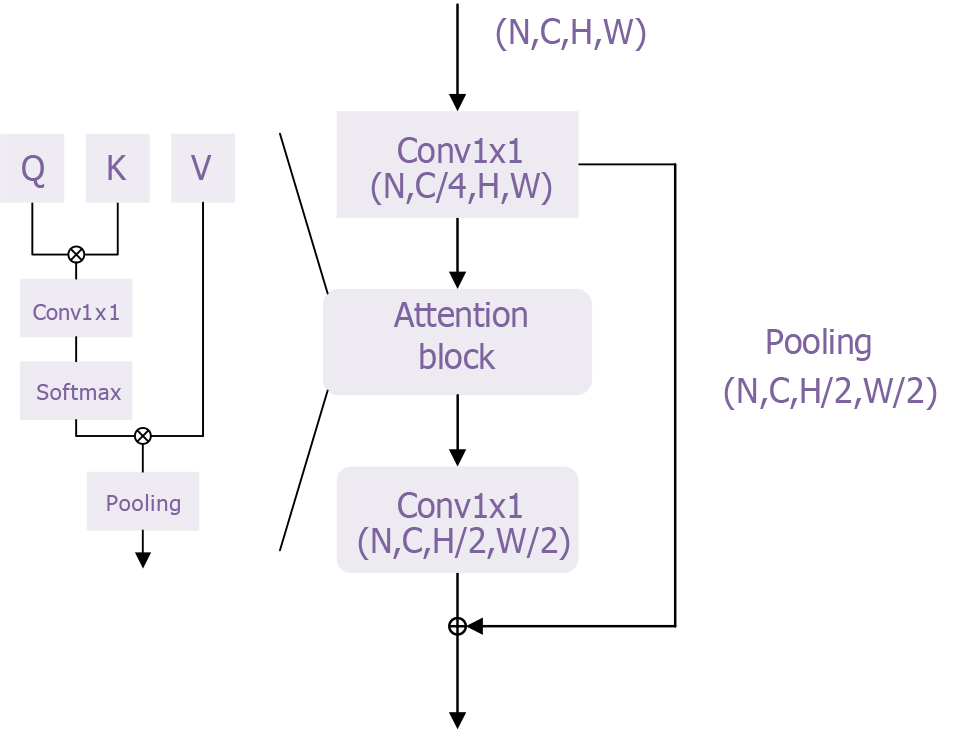

In this study, we adapted the basic transformer model proposed by Chen et al[34] to develop a classification model for esophageal cancer. The overall network architecture is shown in Supplementary Figure 1, with the transformer module illustrated in Figure 4. This transformer module overcomes the limitations of traditional sequential models by addressing the inefficiencies of recurrent neural networks in processing long sequences and mitigating the vanishing gradient problem, enabling the model to handle longer sequences effectively. Additionally, its self-attention mechanism enhances the model’s representational power by better capturing contextual information and long-range dependencies, thereby improving both expressiveness and accuracy.

To further improve model performance, it is crucial to minimize information loss, particularly regarding high-frequency components such as texture details within the target. Yao et al[20] addressed this by modifying the transformer structure based on wavelet transforms, enabling the model to extract more frequency domain information and thereby enhance its performance. The wavelets module of the Wave-ViT model is shown in Figure 5.

The wavelets module performs reversible downsampling through wavelet transform, aiming to retain original image details for self-attention learning while reducing computational costs. Wavelet transform is a fundamental time-frequency analysis method that decomposes the input signal into different frequency sub-bands to address aliasing issues. Specifically, discrete wavelet transfor achieves reversible downsampling by transforming 2D data into four discrete wavelet sub-bands. Here, the low-frequency component reflects the coarse-grained structure of the primary object, while the high-frequency component retains fine-grained texture details[35]. In this way, different levels of image detail are preserved in lower-resolution sub-bands without information loss. Additionally, inverse discrete wavelet transform can be used to reconstruct the original image in the wavelet ViTs. This information-preserving transform enables the design of an efficient transformer block with lossless and reversible downsampling, facilitating self-attention learning on multi-scale feature maps.